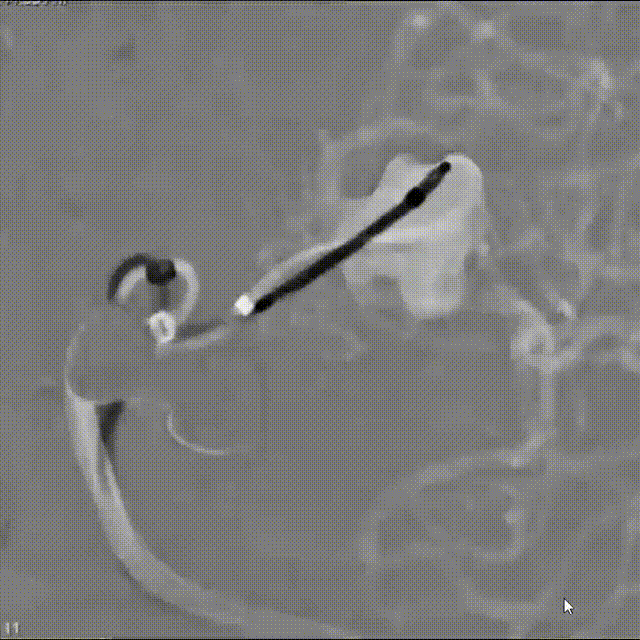

WEB™经由VIA™微导管缓慢推送至微导管头端。缓慢推出WEB™从种子至萌芽状态,继续向瘤腔内远端缓慢推送WEB™至萌芽至开花间状态;将WEB™送至瘤顶,固定WEB™推送杆回撤VIA™,WEB™完全释放。

经造影可见WEB™尺寸合适,贴合瘤壁。解脱后,再次造影可见动脉瘤瘤腔内有明显造影剂滞留。WEB™对分支血流有影响,使用支架保护分支。

术后6个月随访造影,WEB™充分栓塞,瘤颈残留,WEB™被压缩。